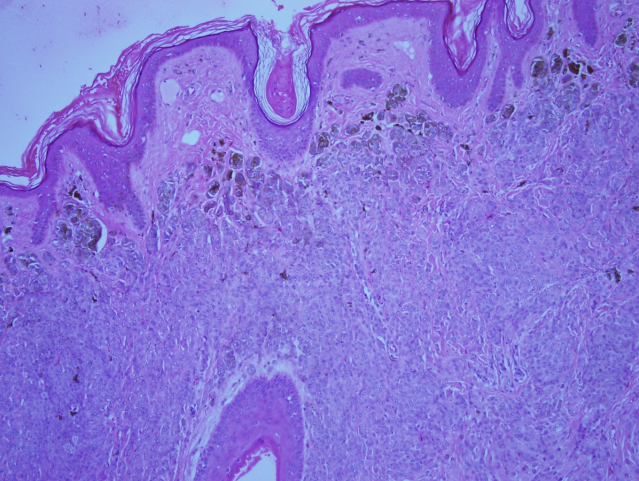

All the specimens collected were sent to the histopathology lab and the report revealed that the specimens had nests and diffusely cellular sheets of benign melanocyte with superficial focal pigmentation and deep dermal maturation. Lateral margins and deeper margins were involved. Overall, there was no malignancy reported (Figure 8 [Fig. 8], Figure 9 [Fig. 9]).

Figure 9: High-power view shows intact dermo-epidermal junction with pigmented melanocytic nests in the superficial part of the nevus.